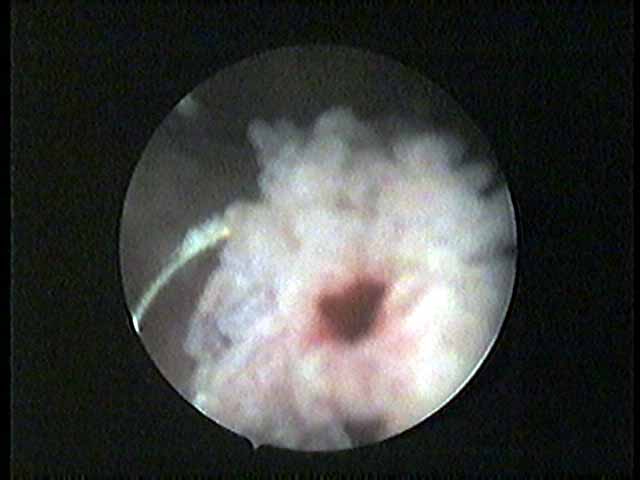

Click/Zoom ที่เห็นเป็นสีแดงนี้ คือบริเวณโคนตอของเนื้องอกที่ถูกตัดออกมาแล้วแต่ยังไม่หมด และหมอกำลังเฉือนซ้ำลงไปอีก เพื่อเอาออกให้หมด

Click/Zoom ลวดที่ร้อนแดง กำลังจี้ตัดเลาะเอาเนื้องอกที่หลงเหลือออกให้หมด เห็นแขนงน้อยที่เพิ่งถูกตัดติด loop ออกมาไหม ยังกะลูกตุ๊กแกแน่ะ